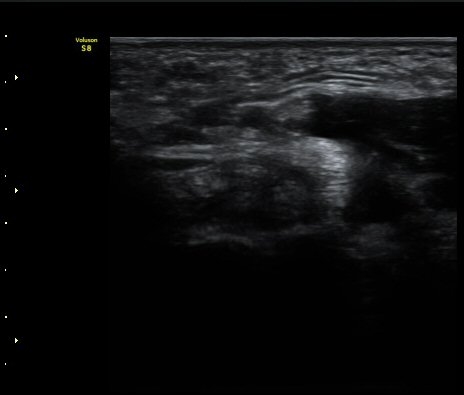

ÃÊÀ½ÆÄ °Ë»ç

¤º